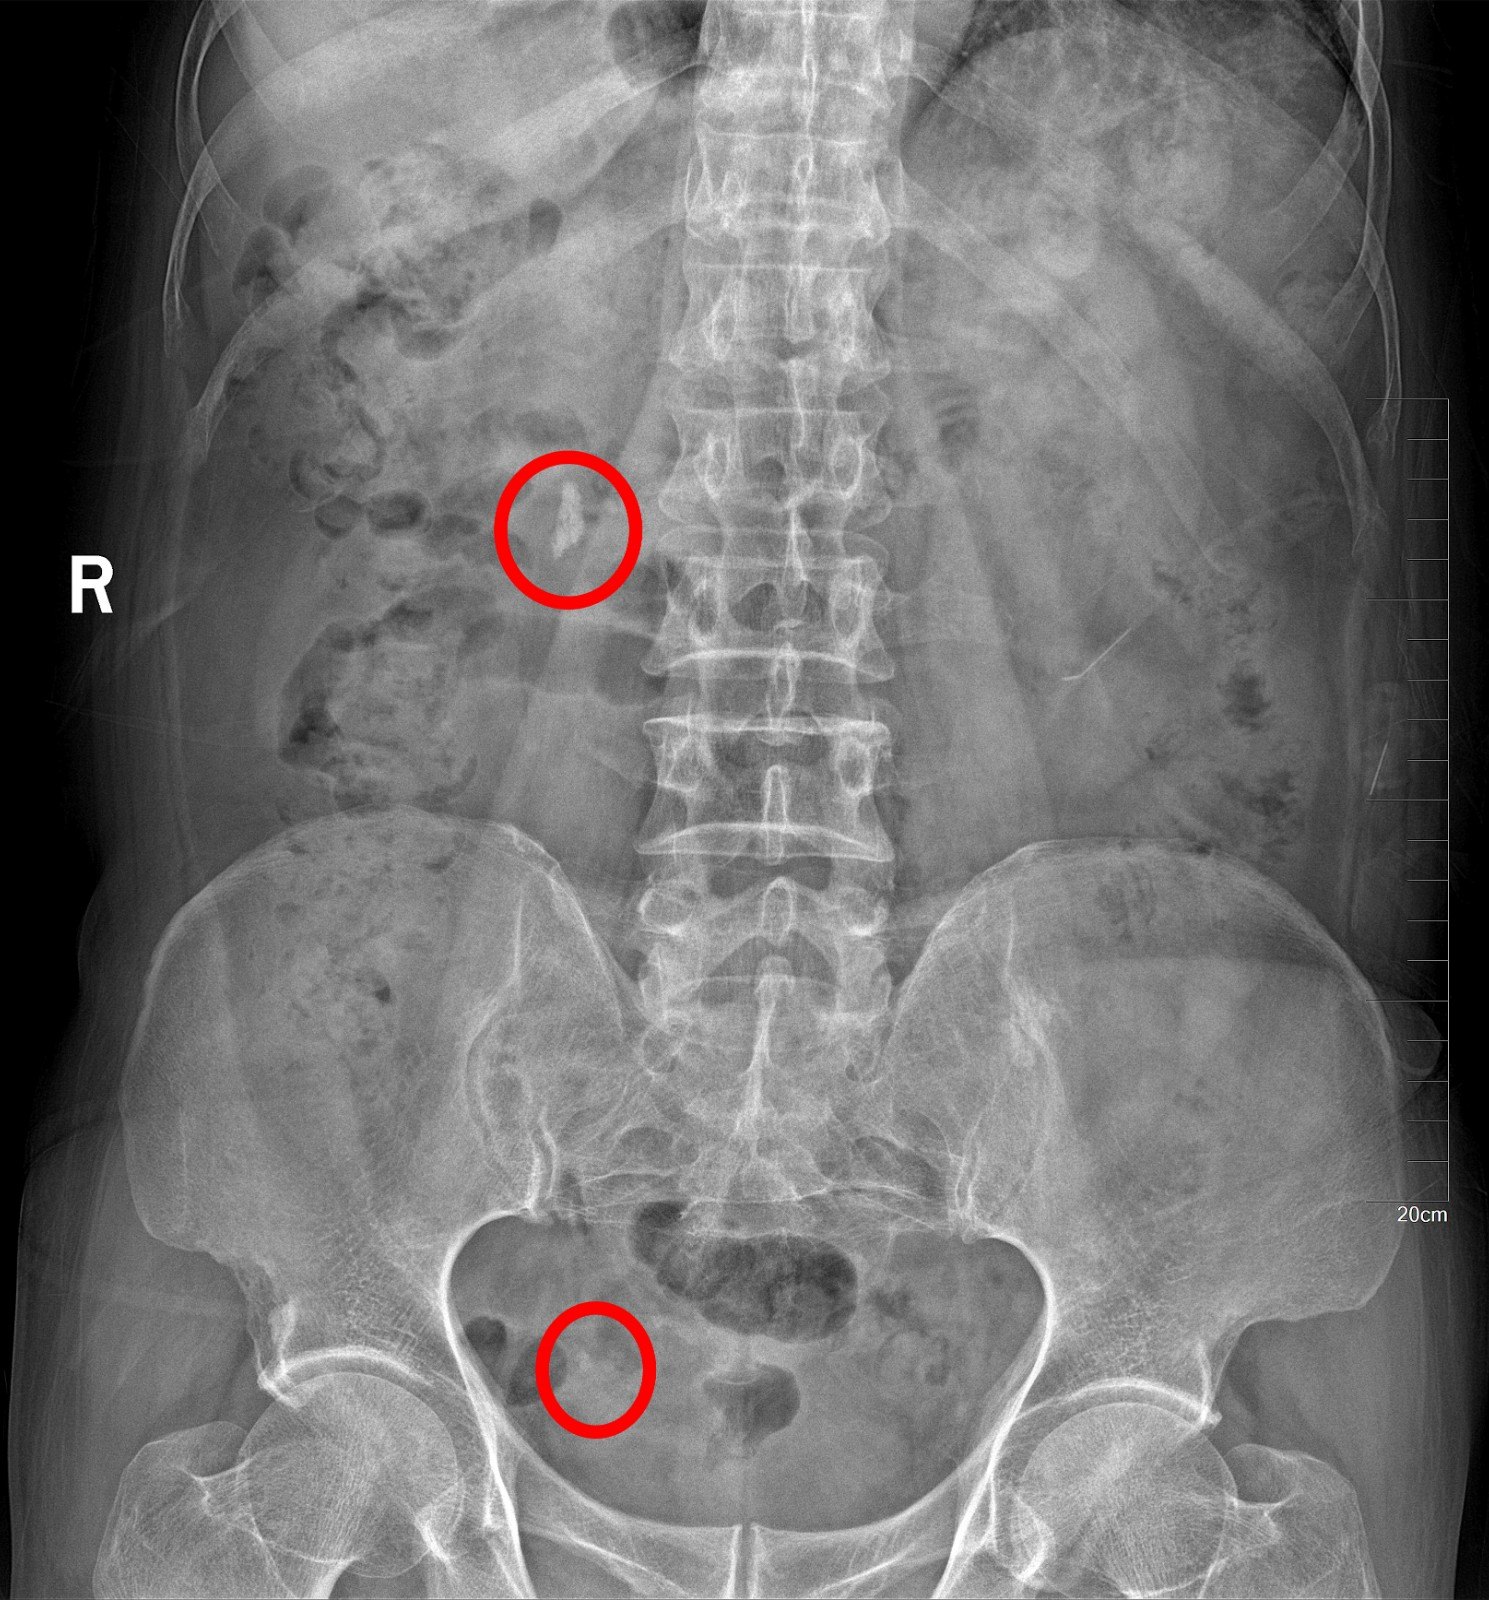

KUB提示右输尿管下段结石呈石街样排列,引起右输尿管完全梗阻,导致右肾萎缩

2016年04月手术患者,女性,32岁,昆山人,五年前曾因右输尿管结石引起肾绞痛于当地消炎补液解痉排石处理,疼痛缓解后未于重视,其间从未予复查,2周前出现右腰痛,与当地诊所就诊后予以震波碎石无效,并出现发热,急诊来我院就诊,CT:右肾萎缩,右侧肾脏积水,右侧输尿管多发结石形成石街约4.5*1.5cm,GFR:右侧17.2ml/min,左侧43.2ml/min。因左侧健肾代偿,肾功能正常:Cr 132umol/L;术前诊断:右输尿管下段多发结石 右肾萎缩 肾功能不全,鉴于右输尿管结石梗阻时间太长,肾功能不全,已处于失代偿期,最终也只能行右侧输尿管下段切开取术,解除输尿管下段梗阻,尽可能保护已经萎缩的肾脏,该患者预后不良。